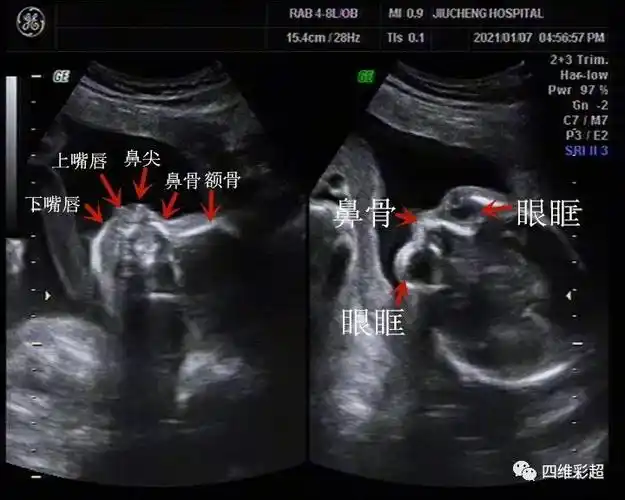

经典病例之鼻塌中面部发育不良binder综合征

binder综合征是颅颌面外科的常见疾病,其发病机理目前还不是十分清楚.